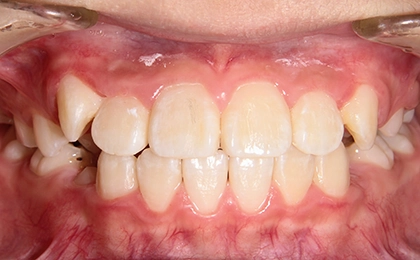

Case1 前歯のガタガタ、部分的な受け口

Before

治療内容 | 上のあごに固定式の拡大装置を装着し、あごを拡げてできた隙間で上の前歯のガタガタを治療し、永久歯列に生え変わるまで経過観察を行いました。 |

治療のリスク | 歯の生え変わりにより拡大装置が合わなくなることがあります。 |